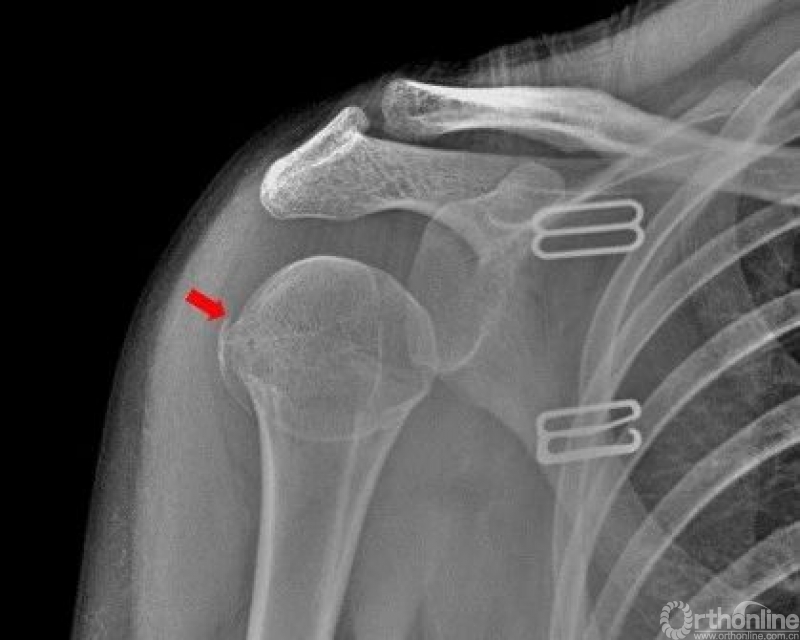

肩关节

右侧肱骨大结节骨皮质欠光整,见弧形透亮线。右侧肱骨大结节骨折